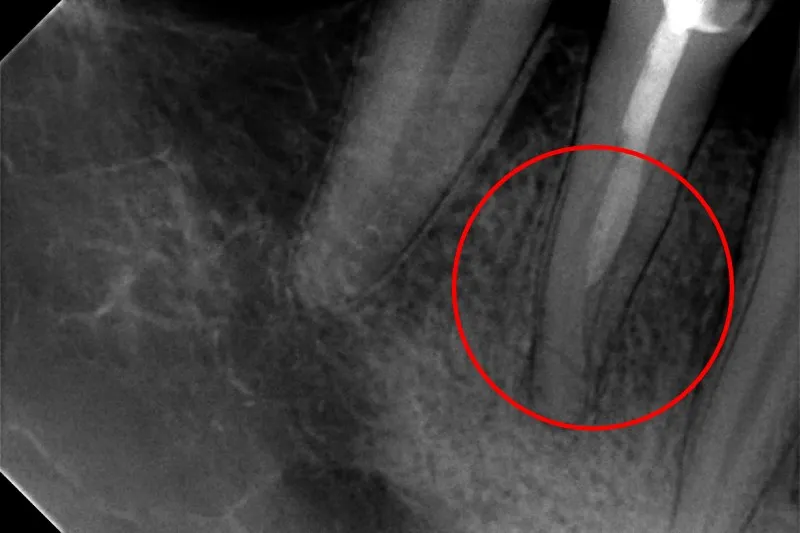

Ciemna plama na zdjęciu: jak wygląda stan zapalny wokół korzenia?

Na zdjęciu rentgenowskim jednym z najważniejszych sygnałów jest tak zwane "przejaśnienie okołowierzchołkowe". To ciemniejszy obszar wokół wierzchołka korzenia zęba, który oznacza zanik kości spowodowany stanem zapalnym. Może to być ziarniniak lub torbiel zmiany, które są bezpośrednim wynikiem nieleczonej infekcji miazgi. Widząc taką "ciemną plamę", wiem, że ząb wymaga leczenia kanałowego, nawet jeśli pacjent nie odczuwa żadnych dolegliwości bólowych.

Jak głęboko sięga problem? Ocena ubytku próchnicowego na rentgenie

Zdjęcie RTG jest również niezastąpione do oceny głębokości ubytku próchnicowego. Pozwala mi precyzyjnie określić, czy próchnica dotarła już do komory zęba, gdzie znajduje się miazga. Często na powierzchni zęba ubytek może wydawać się niewielki, ale na rentgenie okazuje się, że rozprzestrzenił się on znacznie głębiej, zagrażając żywotności miazgi.